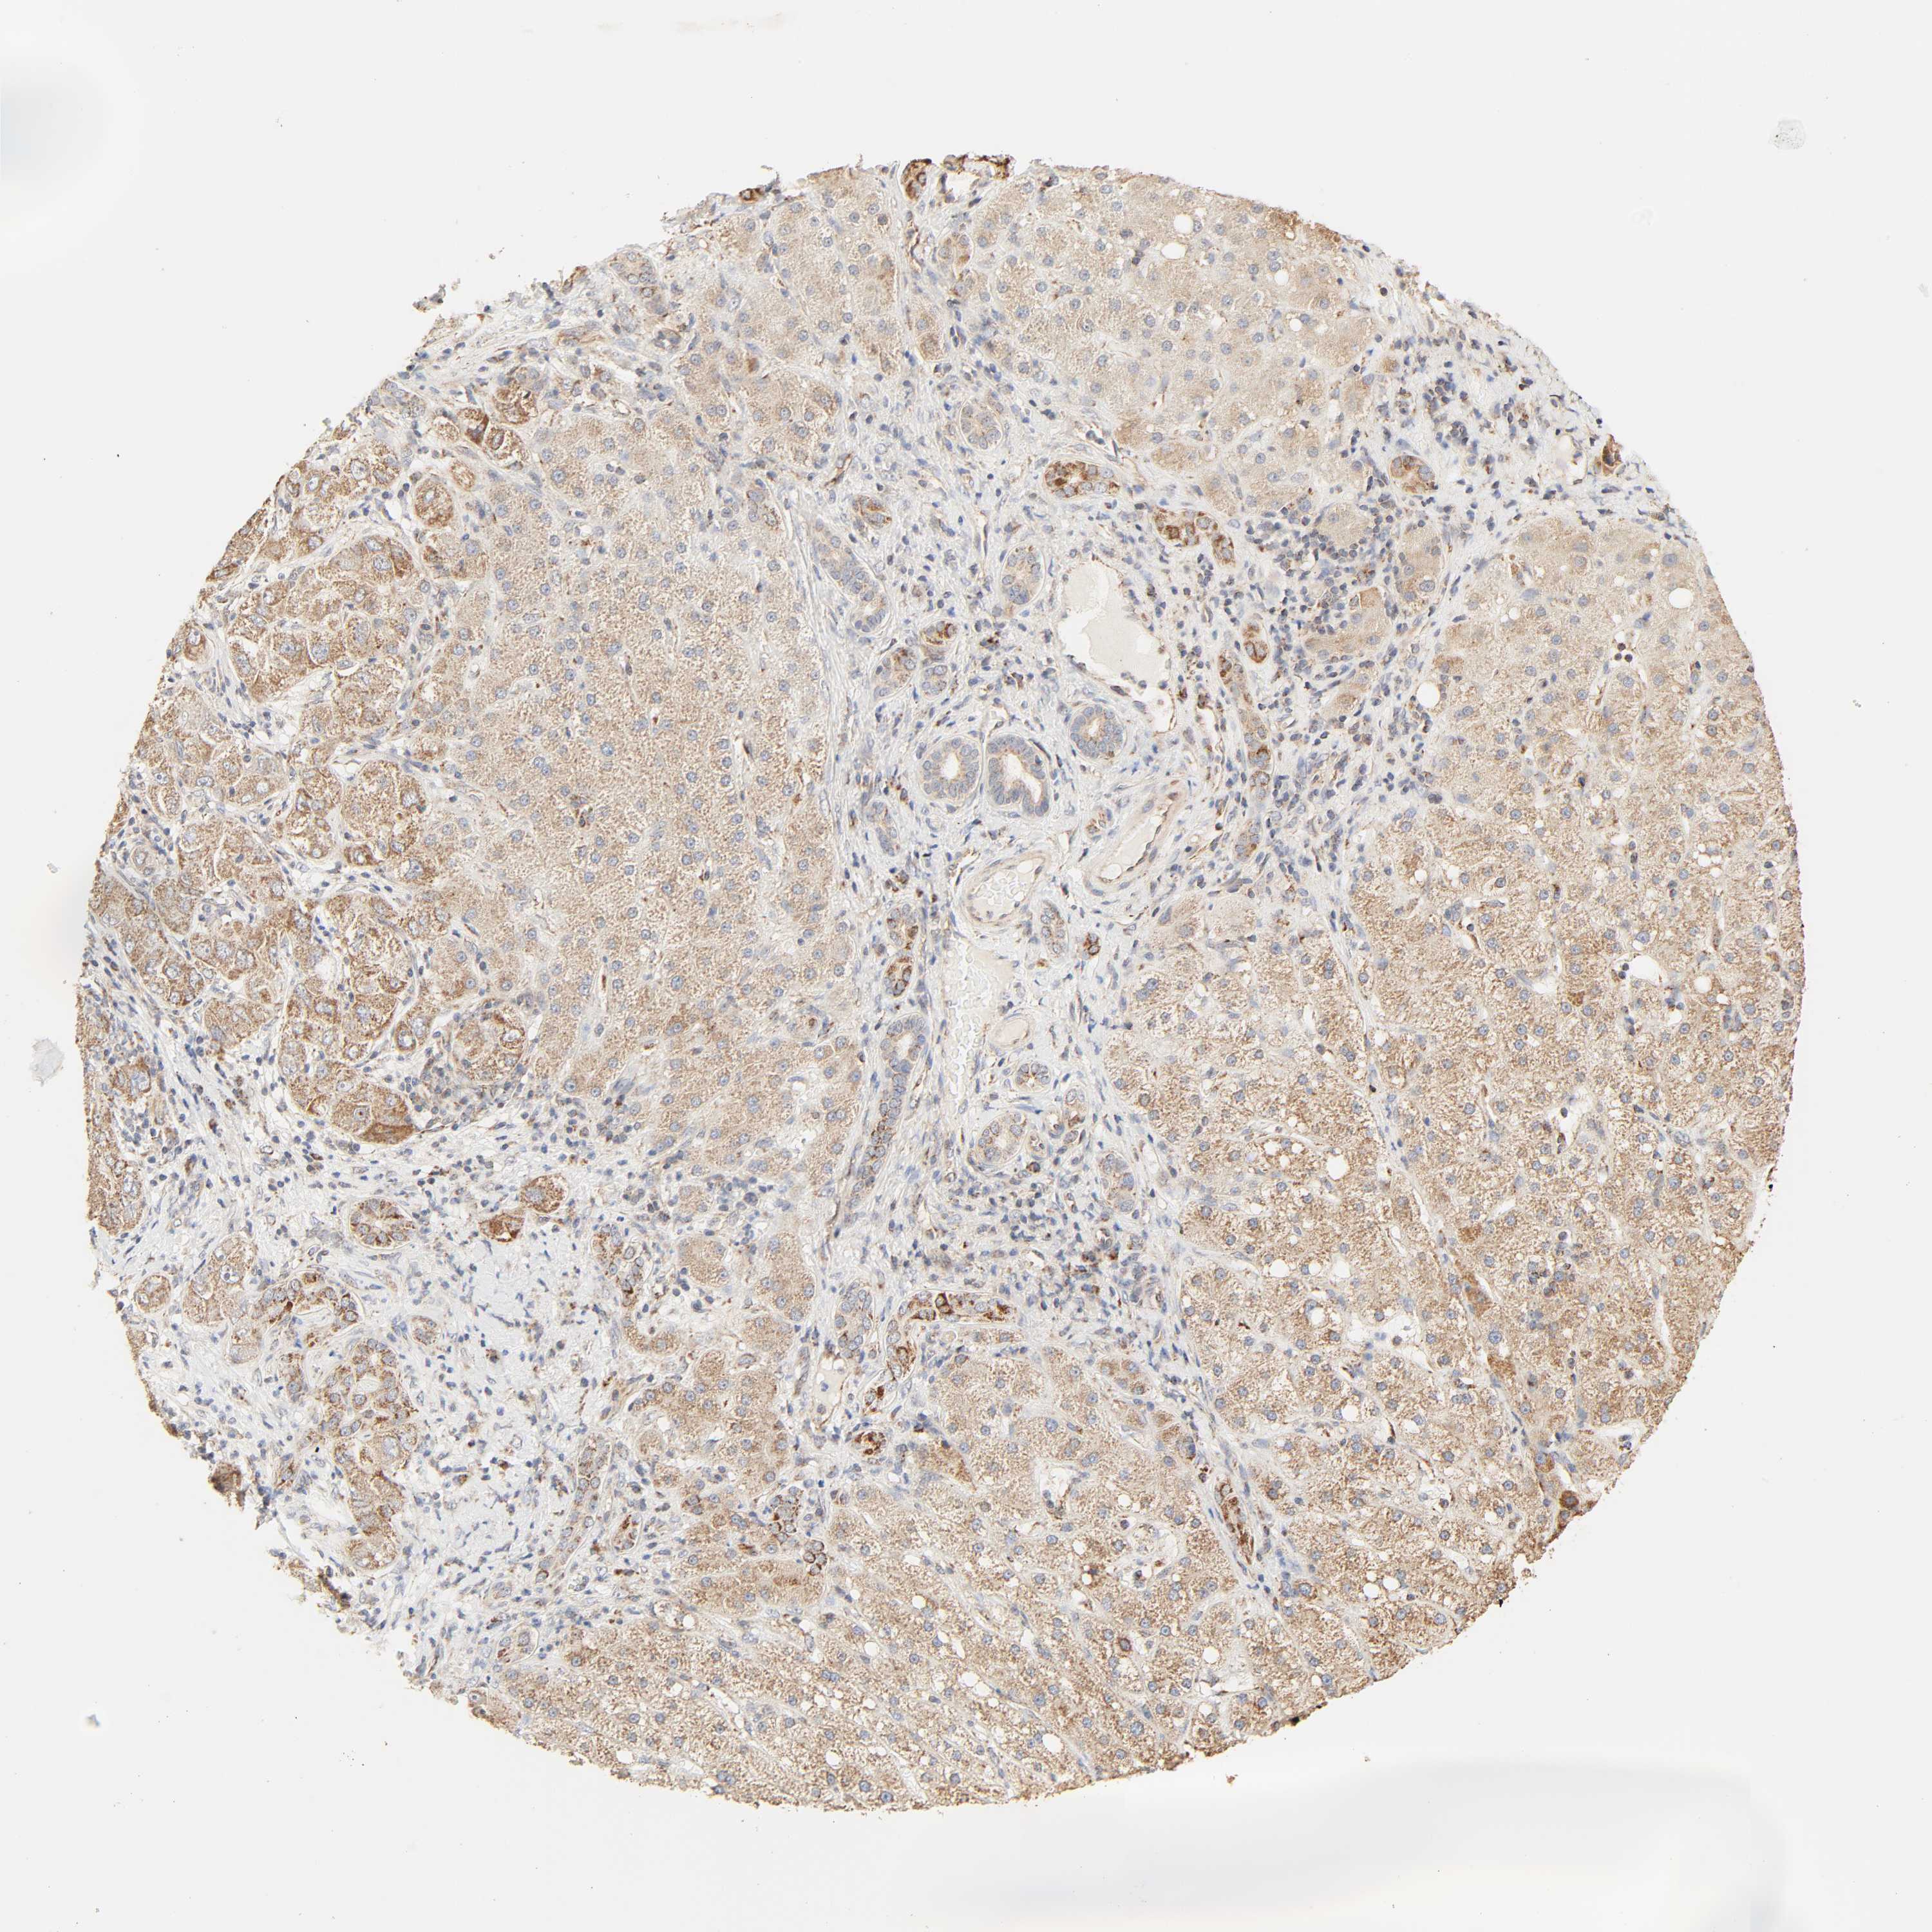

LIVER CANCER - Protein expressioni

A mouse-over function shows sample information and annotation data. Click on an image to view it in a full screen mode. Samples can be filtered based on level of antibody staining by selecting one or several of the following categories: high, medium, low and not detected. The assay and annotation is described here.

Note that samples used for immunohistochemistry by the Human Protein Atlas do not correspond to samples in the TCGA dataset.

Antibody stainingi

Antibody staining in the annotated cell types in the current human tissue is reported as not detected, low, medium, or high, based on conventional immunohistochemistry profiling in selected tissues. This score is based on the combination of the staining intensity and fraction of stained cells.

Each image is clickable and will lead to virtual microscopy that enables deeper exploration of all samples and also displays staining intensity scores, fraction scores and subcellular localization as well as patient and tissue information for each sample.

Antibody HPA004858

Staining

High

Medium

Low

Not detected

Intensity

Strong

Moderate

Weak

Negative

Quantity

>75%

75%-25%

<25%

None

Location

Nuclear

Cytoplasmic/membranous

Cytoplasmic/membranous,nuclear

Cholangiocarcinoma

Carcinoma, Hepatocellular, NOS